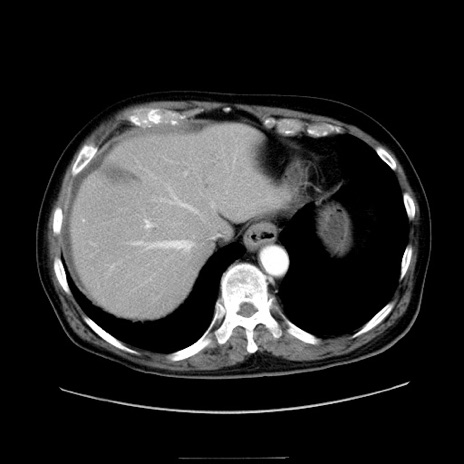

症例30(横断像)

【症例】80歳代男性

【現病歴】約6時間前から臍下部痛が出現。次第に腹部膨隆・背部痛も生じてきたため来院。背部痛の場所は変化しない。

【身体所見】意識清明、BT 36.3℃、BP  131/87mmHg、P 87bpm、SpO2 100%(RA)、臍周囲自発痛・圧痛あり、反跳痛なし、自発痛部位に一致して板状硬あり、腹部膨隆、腸雑音減弱、CVA tenderness両側陰性。

【データ】WBC 19600、CRP 0.33

冠状断像